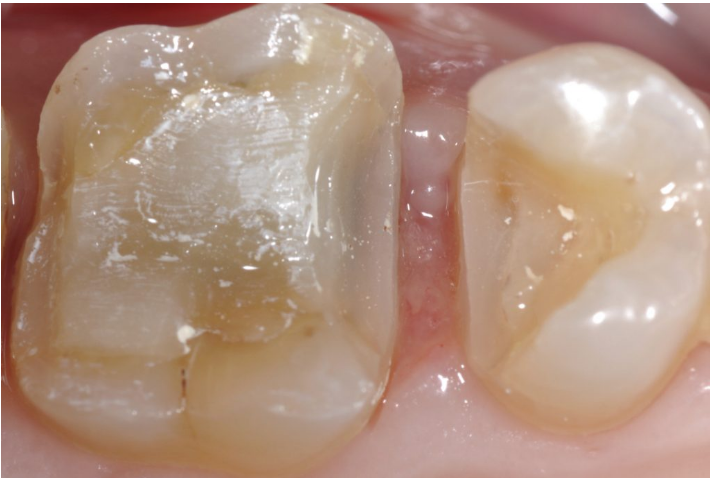

图一:患者男,47岁,因牙龈出血而来,原因可能是由于25、26、27邻接点的丧失导致的。目前25、26、27邻面的旧修复体为16年前进行修复的,使用了双固化复合树脂作为牙本质替代体,行嵌体修复。这次的治疗方案是:使用3个铸瓷修复体重新恢复邻接关系,替代原修复体。